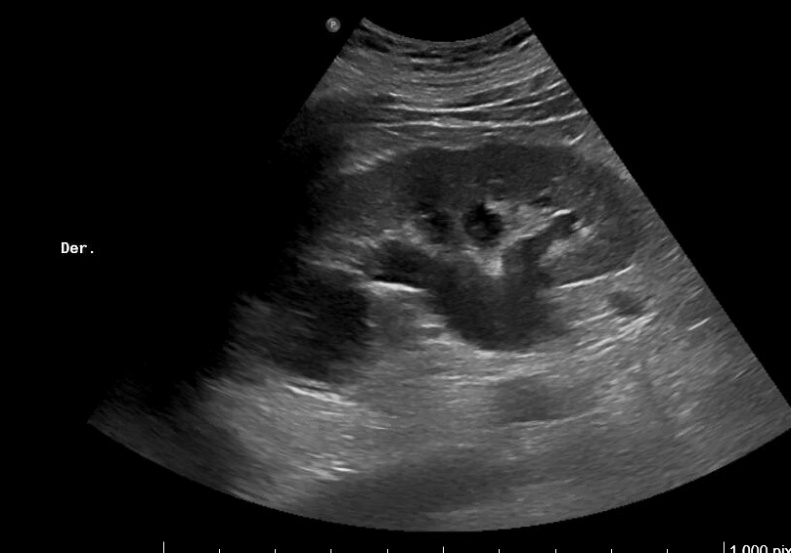

Imagen 4. Ecografía de vejiga y próstata: Corte sagital. Vejiga distendida con paredes engrosadas. Crecimiento del lóbulo medio prostático que impronta en vejiga. Volumen aproximado de 127 cc.